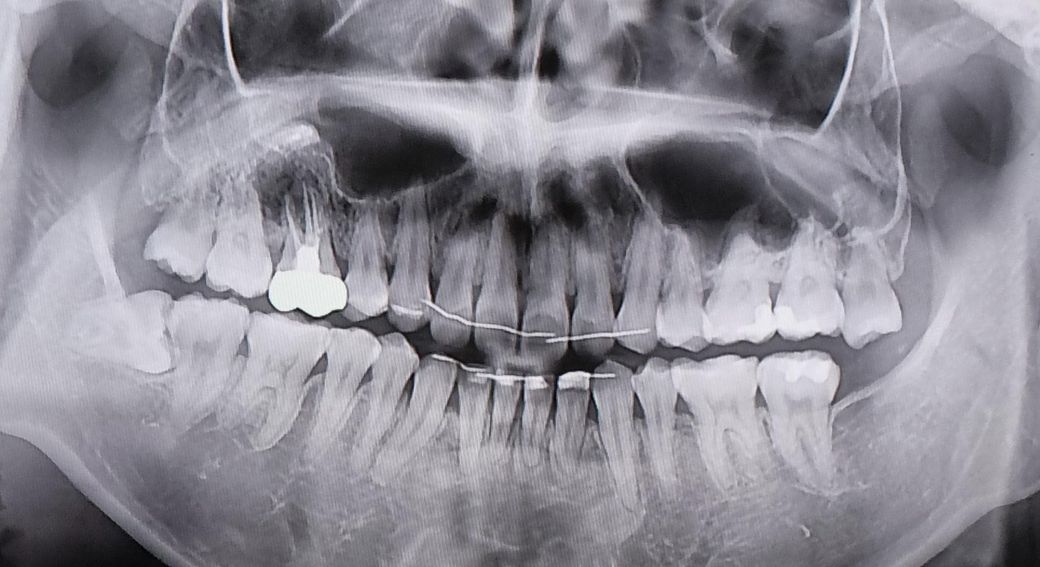

왼쪽에 신경치료 후 크라운을 씌운 치아의 뿌리에 염증이 생겼고, 최근에는 염증이 사진상 인접한 왼쪽 치아까지 번진 것으로 보여서 두 치아 모두 임플란트 치료가 필요하다는 진단을 7월말에 받았습니다.

현재는 왼쪽 치아 두 개에 염증이 진행된 상황이지만, 혹시라도 경과를 지켜보는 사이에 오른쪽 인접 치아까지 염증이 퍼져 임플란트를 세 개나 해야 하는 상황이 되지는 않을지 매우 걱정스럽습니다.

• 1번 째 사진